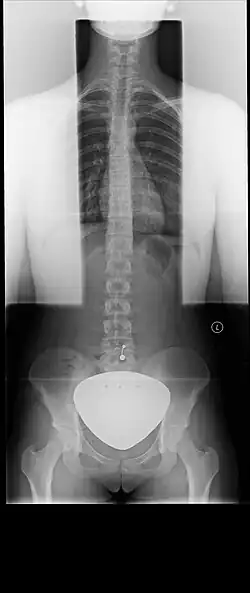

X-ray of the spine with a gonadal shield in place. Use of the gonadal shield is no longer recommended as it results in more radiation being used to produce the image, and does not protect against internal scatter.

Starting in the 1950s, lead shielding began to be used on patients during all X-rays over the abdomen to protect the gonads (reproductive organs) or a fetus if the patient was pregnant. Dental X-rays would also typically additionally use lead shielding to protect the thyroid. However, a consensus was reached between 2019[4][5][3] and 2021[6][7] that lead shielding for routine diagnostic X-rays is not necessary and may in some cases be harmful. In part, this is due to improved understanding of the effects of radiation on patients, as the amount of radiation patients were exposed to in routine X-rays and CT scans was found to not affect fertility or a developing pregnancy. It was also due to the improvement of X-ray machines. For instance, older X-ray machines would use a set amount of radiation, and used film which requires more X-rays.[3] Modern X-ray machines are digital, and automatically use the minimum amount of radiation needed to image the patient, which means overall the radiation levels are much lower than in the past; however, if the lead shield is in the field being imaged, the machine will produce more X-rays in order to attempt to penetrate the lead shield. Additionally, if the shield is in the field, this may affect the image produced, requiring a second X-ray to be performed, which would also lead to overall increased radiation exposure. Additionally, patient shielding is ineffective at reducing internal scatter; because only a portion of the patient is shielded, X-rays may still go through the gonads or fetus from bouncing off the imaged areas internally.[8]